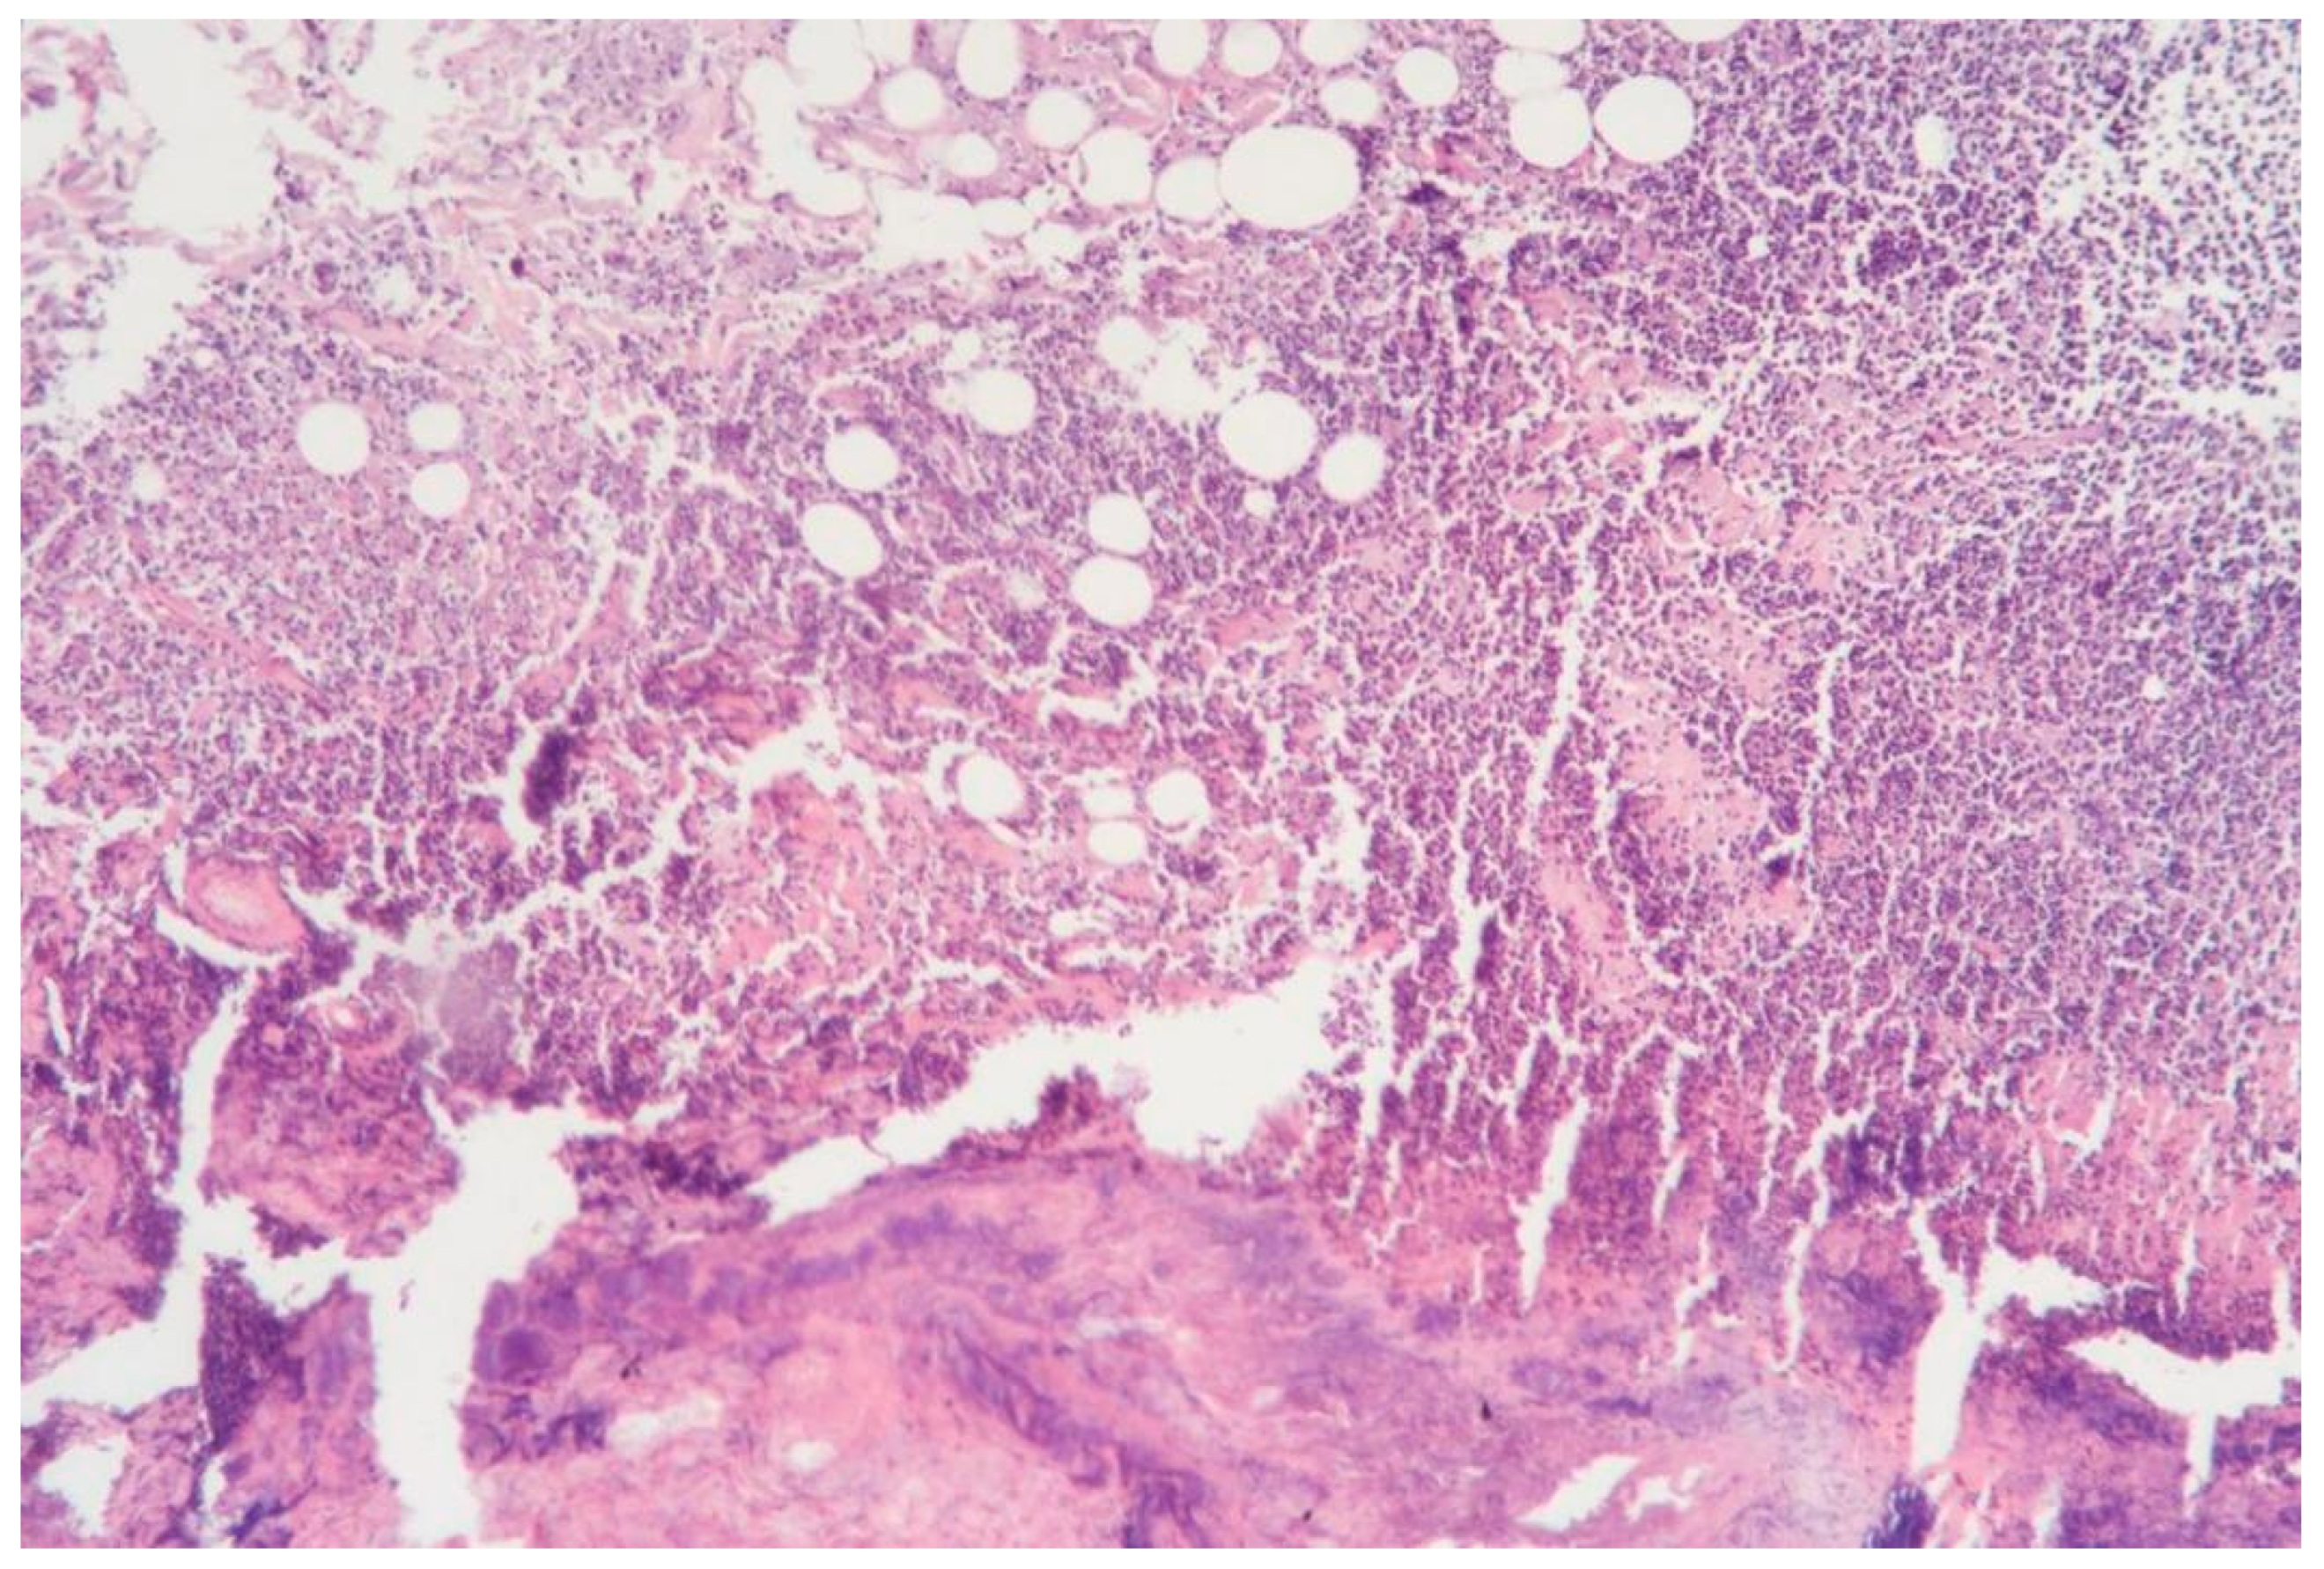

3.1.1. Clinical Case 1: Soft Tissues in the Dissection Area, Scar 10 W (See Figure 2)

Description: The histological examination revealed total necrosis of the epidermis and dermis, with the formation of a demarcation zone heavily infiltrated by polymorphonuclear leukocytes. The infiltrate extended into the subcutaneous adipose tissue. The vessels within the necrotic zone were coagulated, while those in the underlying tissues were markedly dilated. Small diapedesis hemorrhages were noted. The skin appendages in the underlying tissues remained intact, and the collagen fibers were preserved.

Figure 2.

Skin changes in Rat 1 on the 7th day after exposure to the thulium laser at 10 W, 65 Hz. H&E staining, 10× objective magnification.